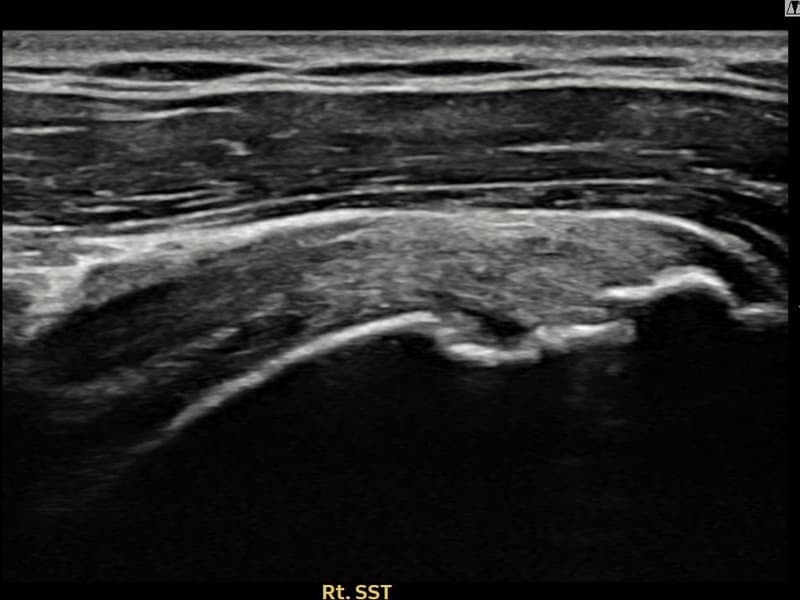

시술 전 초음파 측정 결과 파열 크기는 13mm × 6mm (힘줄 두께의 약 62% 결손)로 확인되었습니다. 시술 전 초음파에서 우측 극상근건 점액낭면측의 광범위한 에코 단절과 힘줄 두께의 현저한 감소가 확인되었습니다. 시술 후 초음파에서 점액낭면측 힘줄 경계가 선명해지고 연속성이 완전히 회복된 것이 관찰되었습니다.

40대 후반 남성 환자분으로, 골프를 즐겨 하시다 스윙 동작 중 어깨에 통증이 생겨 운동을 중단하셨습니다. 이후 통증이 악화되어 팔을 앞으로 뻗거나 위로 올리기도 어려운 상태가 되어 내원하셨습니다. 초음파 검사에서 우측 극상근건 점액낭면측의 광범위한 부분파열이 확인되었으며, 파열 두께와 범위를 고려하여 초음파 유도 하 축소봉합술을 시행하였습니다. 시술은 당일 귀가로 이루어졌으며, 이후 보조기 착용 6주 후 단계적으로 어깨 근력 강화 운동을 진행하였습니다. 시술 9주 후 추적 초음파에서 점액낭면측 힘줄 연속성이 완전히 회복된 것이 확인되어 골프 복귀에 성공하셨습니다.